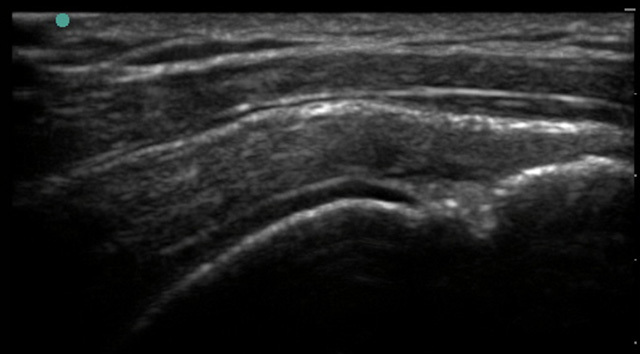

Shoulder Supraspinatus Tear - Concave Appearance Image